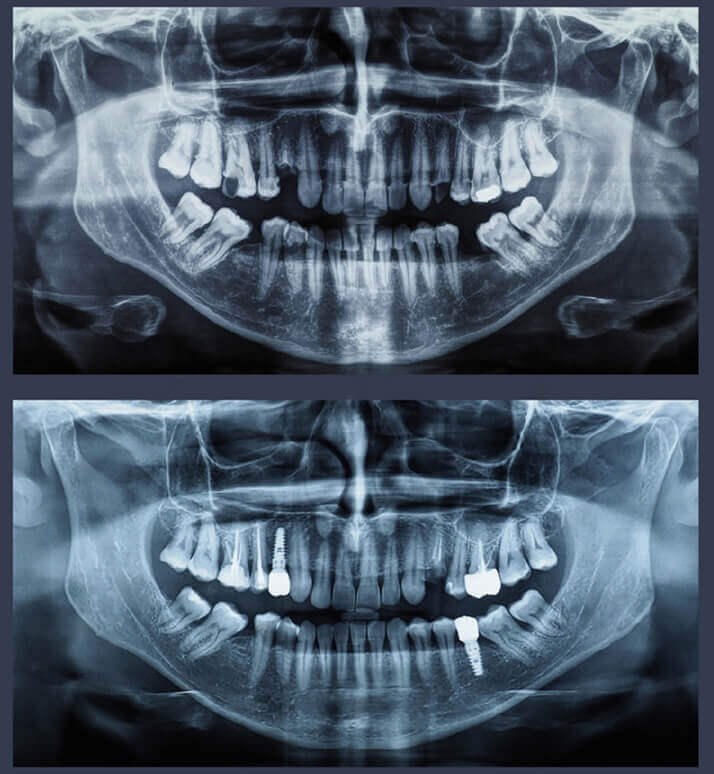

Dental radiologys

Dental radiography is a type of X-ray imaging that is used to capture images of teeth, gums, and other oral structures.